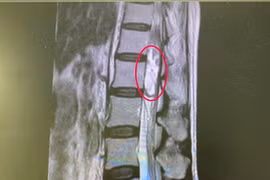

Với sự hỗ trợ của kính vi phẫu hiện đại, các bác sĩ bệnh viện Đa khoa Bãi Cháy đã thành công lấy toàn bộ khối u tủy kích thước lớn 20x30mm chiếm chọn ống sống, bảo vệ an toàn cấu trúc tủy sống và rễ thần kinh cho bệnh nhân 24 tuổi. Đây là bệnh lý rất nguy hiểm cần phải được phát hiện và điều trị sớm.